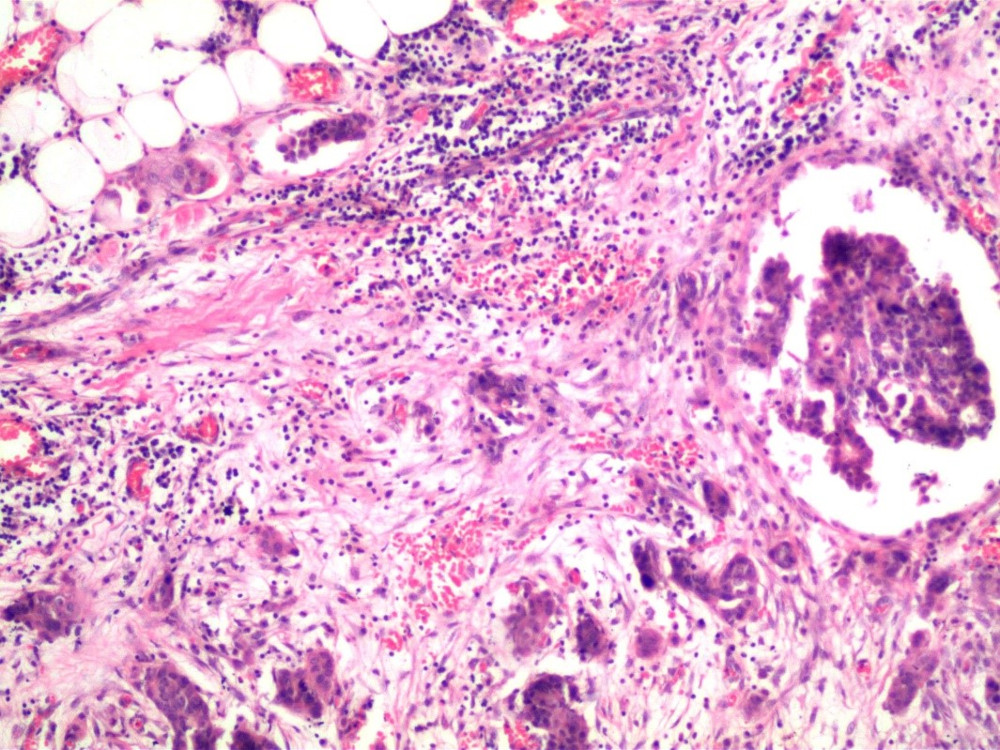

Acude con médico quien solicita Rx de tórax, identificando una lesión parahiliar derecha. Se toma biopsia por punción (FOTOS 1 Y 2)

Figura 1

Adenocarcinoma invasor, predominantemente acinar con áreas micropapilares, no mucoproductor primario de pulmón, con extensión a pleura y tejidos blandos.